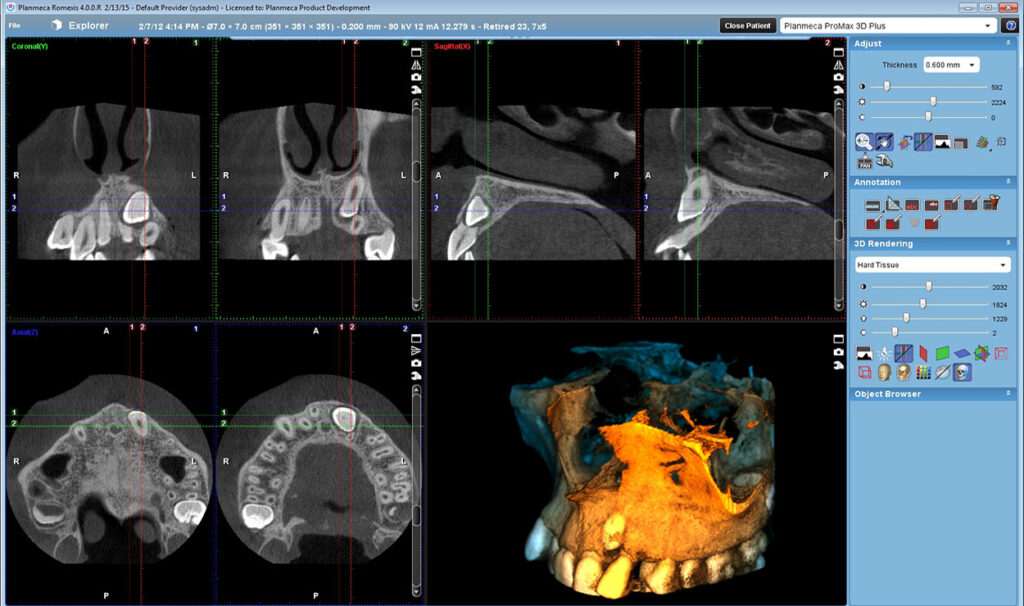

03. Otvaranje 2D i 3D snimaka

04. Navigacija

Srednje polje Ø68×68 mm, niska rezolucija velicina voksela 600 µm